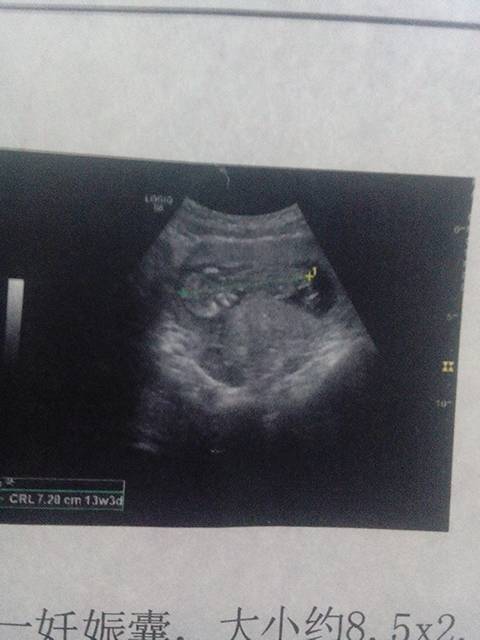

今天去检查子宫前位,宫体增大,宫内见一妊娠囊,大小约8.5x2.9cm,内见一成形胎儿,胎心胎动好 今天去检查子宫前位,宫体增大,宫内见一妊娠囊,大小约8.5x2.9cm,内见一成形胎儿,胎心胎动好,CRL:7.3cm ,结果是不是胎儿发育很好呀?,是男孩还是女孩呀, 点击展开 ”小情绪 2014-12-29 12:13 为您推荐: 其他回答 不一定的! 琳子💄 2014-12-29 17:35 男孩女孩看不出来 954451988爱你 2014-12-29 14:38 ……………… 々桴花蘿尽乀为你綬这倥絾 2014-12-29 13:16 看不出来,宝宝还小 151*****406_Kqzf 2014-12-29 12:48 祝宝妈好孕 180*****957_KEdj 2014-12-29 12:43 加载更多 相关问题 老婆自己算从上次月经第一天到现在是大概52天 B超检查单描述: 子宫前位,径线增大,妊娠囊于宫 今天做了孕检,胎心144,妊娠线直细到接近两乳间,胎动左右都动!不知是男孩还是女孩? 过期妊娠是不是剖宫产的手术指征,过期妊娠一定要剖腹产吗(胎心,胎动都正常)?